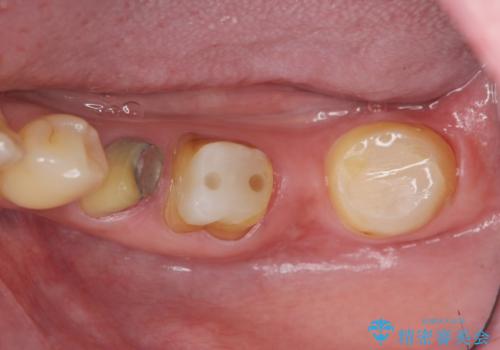

- 110万円(インプラント×2・チタンカスタムアバットメント×2・ジルコニアクラウン×3・仮歯×3 ・遊離歯肉移植術)費用は治療当時の料金となります

インプラント周囲のお掃除のしやすさを高め、長期的な予後を見込むために、遊離歯肉移植術を行っています。